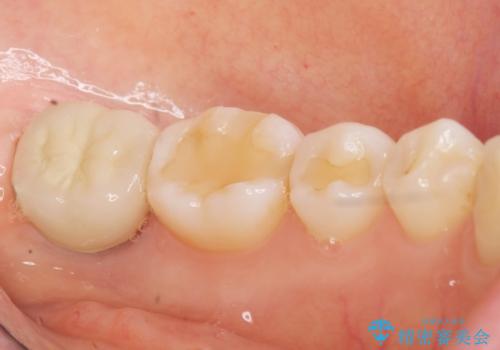

割れている奥歯を抜去後左上の機能していない親知らずを移植し、生着したのち根管治療・補綴を行いました。

インプラントや義歯を用いることなく咬合を回復することができ、喜んで頂けました。

被せ物の種類:メタルボンドクラウン エコノミー フルベイク